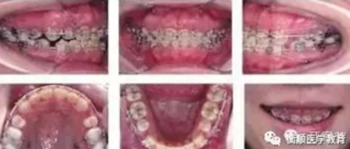

患者口外情況為凸面型,頦部左偏約1mm?;颊呖趦惹闆r為恒牙列;雙側磨牙中性偏近中關系,前牙開牙合Ⅰ°,約1.5 mm,覆蓋為1mm;上牙列Ⅰ°擁擠3 mm,下牙列Ⅰ°擁擠2mm;上中線右偏約1.5mm,下中線基本正。診斷:安氏Ⅰ類,骨型為Ⅱ類,高角面型。

圖1 患者治療前面相